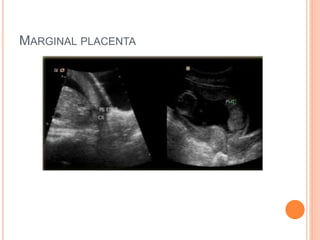

MARGINAL PLACENTA